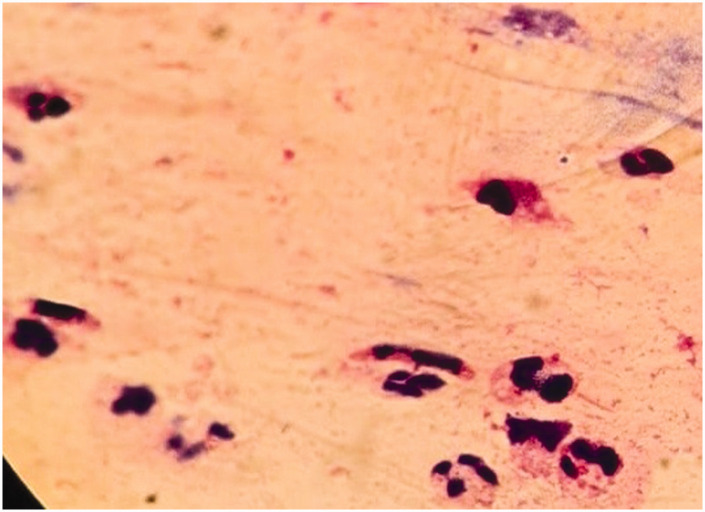

ObjectiveThe objective of this study was to examine the applicability of shear wave elastography as a quantitative approach for measuring tissue stiffness in the differentiation of intra-abdominal abscesses from hematomas, which share similar radiological findings.MethodsThis prospective single-center study included patients with intra-abdominal abscesses or hematomas who underwent shear wave elastography prior to ultrasound-guided drainage in an interventional radiology clinic between 2021 and 2022. An independent samples t-test was used to compare the mean shear wave velocity between the abscess and hematoma groups.ResultsA total of 50 patients (33 with abscesses and 17 with hematomas) were included in this study. The elastography values of the patients were expressed as mean ± standard deviation (minimum-maximum). The mean shear wave velocity of hematomas (1.11 ± 0.41 (0.54-1.98) m/s) was significantly higher than that of abscesses (0.68 ± 0.16 (0.36-1.07) m/s) (p < 0.001). In the receiver operating characteristic analysis, the area under the curve was 84.8%. When the optimal cutoff value was defined as 0.72, the sensitivity and specificity were 82.4% and 67%, respectively.ConclusionShear wave velocity can aid in differentiating intra-abdominal abscesses from hematomas using a simple and widely available method.